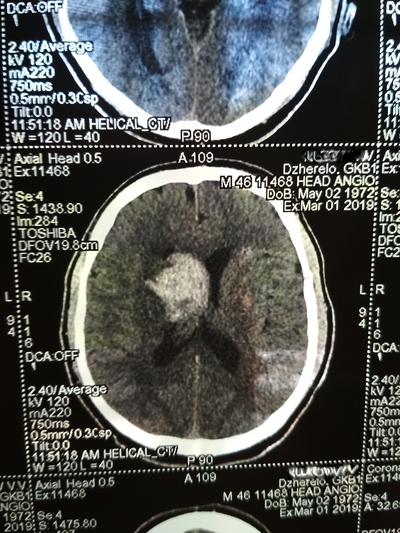

День не помню, возможно 1-2 марта, открываю глаза, а вокруг суета и непонятная обстановка. Осознаю что я а больнице, меня перетягивают с кровати на носилки и куда-то катят и тащат, укрыли сверху одеялом, внесли на улицу, очень холодно. Притащили (по другому не назовешь) меня на компьютерную томографию, перекинули с носилок на стол КТ, голову уложили в ячейку для головы и чем-то расклинили, чтобы не шевелился, больно капец. Я уже осознал что нахожусь в больнице, но что произошло не могу понять, да и думать мне было очень больно в голове.

Вернули меня в палату, перекинули на койку, и мои родные начали рассказывать, что 22 февраля мне стало плохо, качало, тошнило и рвало, жена подумала, что я выпил с друзьями в гараже. Потом вызвали скорую, которая померяла давление и там 290 на 160. Что то укололи. Потом возили в одну в больницу, они отказались принимать, повезли в другую. Вот так с 26 февраля я оказался в "еврейской", это у нас так называют гкб1. (городская клиническая больница № 1) По компьютерной томограмме врач определил геморрагический инсульт и аневризма, вот описание что это такое:

Пример аневризмы сосудов головного мозга

После КТ со мной общался врач, видя, что я уже в сознании, трогал руки ноги, просил потянуть рукой его руку, у меня плохо слушалась правая сторона тела.

Ещё врач сказал что желудочки головного мозга заполнились вытекшей кровью и они решают или вскрывать черепушку или медикаментозно лечить.

Вот тут я пересрал, совершенно не хотел проветривать бестолковку (но обрадовался когда на снимках всё таки обнаружили мозг 😁)